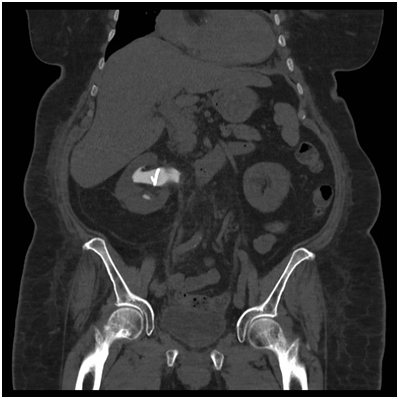

She also has a previous surgical history of appendectomy at age four. In the emergency department, she was found to be febrile to 38.7OC, blood pressure of 156/59, O2 saturation of 91% on room air, blood sugar level of 10.9mmol/L, respiratory rate of 20/min, and pulse rate of 90/min. Examination revealed the presence of bowel sounds, moderate to severe pain and tender right flank and iliac fossa with no guarding, rebound and the presence of bowel sounds. Urine microscopy subsequently demonstrated pyuria and Morganella Morganii was cultured. Blood cultures were negative. Concerns for an acutely obstructed infected right kidney were raised when it was noted that her creatinine was 84umol/L and eGFR was 56. A non-contrast CT was performed (see image) showing right peri-nephric stranding, dilatation of the right pelvicalyceal system to the pyrloureteric junction (PUJ) and no evidence of calculus or other aetiology of the obstruction. There was periureteric fat stranding along, atypical for PUJ obstruction.

Typically, it presents non-specifically and similar to pyelonephritis, with flank pain, fever, haematuria and lower urinary tract symptoms [1-3]. XGP rarely affects both kidneys [4,5]. As in this case, a significant portion of patients have malignancy considered in the differential [1,3,5]. The optimal diagnostic modality has been cited as computed tomography (CT) [1,3]. Its advantages are that it can isolate significant disease in the majority of cases and also demonstrate associated findings such as hydronephrosis, renal parenchymal collections and abscess [1,2] (Figure 2)

The progression of XGP can be divided into three stages, stage 1, where inflammation is confined to the kidney. Perinephric fat is affected in stage two and finally in stage three, the inflammation affects retroperitoneum [2,4]. This case reflects the initiation of the pathophysiological process at the pelviureteric junction. The treatment of advanced XGP is frequently cited as nephrectomy [1,2,5], although cases where antibiotics have been successful have been cited [1,2,5]. Surgical success can also been improved with pre-operative and post-operative antibiotic use [1,5] The prognosis, with treatment of XGP is usually favourable, with rare cases of mortality associated with operative complication, such as sepsis [1,3] (Figure 3).